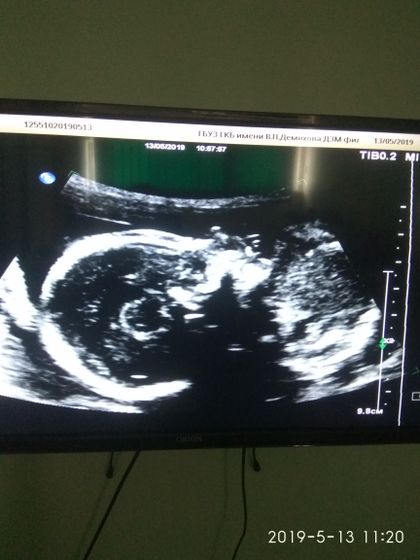

Подтвердили что ждём мальчика.Все довольны кроме дочки))Она с папой тоже присутствовала на Узи, и орала как все полуторагодовалые дети, с истериками)Но да ладно, подрастет и поймет что была не права)